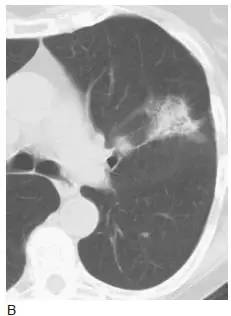

图9 弥漫性细支气管肺泡癌(BAC)

A. 伴双肺实变的BAC;

B. 伴两肺模糊小结节;

C. 同一患者高分辨率CT 显示弥漫分布的小结节